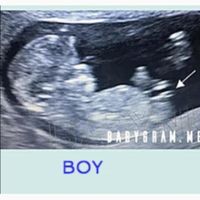

Holaa chicas hoy fui a mi primera ecografía y todo esta perfecto 😍 alguien sabe decirme por algun método si creen que es niña o niño? Muchas gracias de antemano